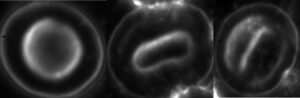

Babesia in a red blood cell – under dark-field microscopy

The spectrum of disease manifestations is broad, ranging from silent infection to fulminant, malaria-like illness that can cause severe hemolysis — the destruction of red blood cells — and, in some cases, death. Babesia infections therefore range from almost asymptomatic to severe. The specific laboratory diagnosis of Babesia infection is performed through morphological examination of (Giemsa-stained) blood smears, serology, and, with variable success, DNA testing (PCR). Babesia infection causes alterations (protrusions and perforations) on the surface of red blood cells, and the pathogen itself can be identified inside the cells [1][3][4]. High-level infection can be detected through simple microscopic blood examination; in certain confirmed cases, the parasite infected a large proportion of red blood cells [4]. In general cases, concentration of infected red blood cells is required — for example, using the DualDur co-infection preparation method. According to the recommendation of the U.S. Centers for Disease Control and Prevention (CDC), babesiosis is primarily diagnosed through microscopic examination of the blood [5].

Surface changes in red blood cells caused by Babesia – electron microscopic image

Babesia in the red blood cell – electron microscopic image